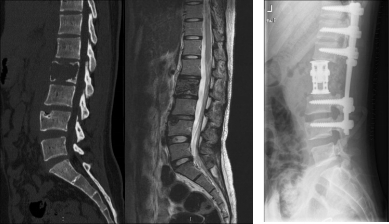

原发脊柱肿瘤的完整根治手术(左图术前,右图术后)